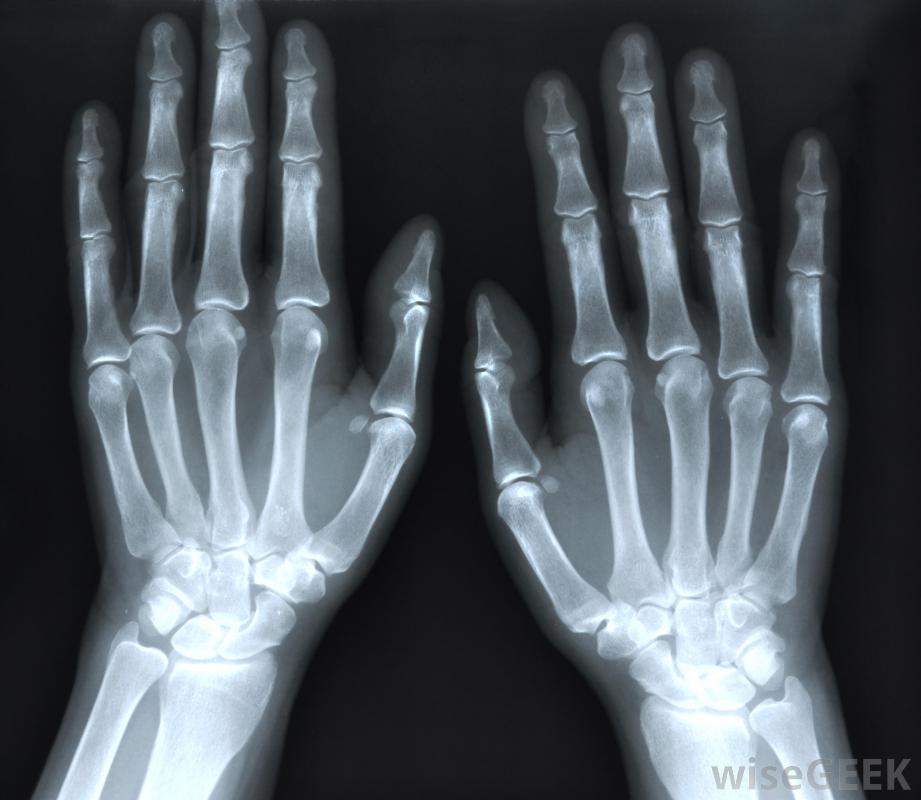

乳清切除術是一種外科手術,用于去除大腳趾上的骨刺。骨刺是關節內細小骨頭的突出物。關節疼痛和運動受限是骨刺最常見的癥狀。大腳趾的關節可能會受到骨刺的困擾并引起劇烈的疼痛疼痛嚴重到日常活動(如行走)受到抑制的程度,可能需要先進的醫療干預措施(如:cheile切除術)來去除骨刺并緩解令人不安的癥狀。切掉可用于去除人的大腳趾上的骨刺。患有關節炎的人通常會出現骨刺。關節炎會導致關節嚴重受損,骨刺通常是為了增加受損關節的表面積而形成的。大腳趾關節炎的發展是一種被稱為拇趾僵硬的疾病。這是足部關節炎最常見的部位之一關節炎患者常出現骨刺。拇趾僵硬可能會因為對大腳趾功能的限制而出現問題當腳趾從地面上推動時,它向上彎曲的運動有助于使行走成為可能患有拇趾僵硬癥的患者,大腳趾可能會變得僵硬,這可能會使行走困難。隨著時間的推移,腳趾的有限運動可能會導致腳趾關節卡滯,從而導致額外的不適。在關節過度受損和出現其他并發癥之前,接受一次全膝關節切除術可以幫助去除現有的骨刺大腳趾關節有時會受到骨刺的困擾,導致劇烈疼痛。拇趾僵硬癥的癥狀各不相同。許多有骨刺的人可以看到隨著馬刺的增長而出現腫塊。僵硬和疼痛,可能是尖銳的或持續的疼痛,也可能存在。最常見的發生在大腳趾根部,如跑步等體力消耗可能加重疼痛、發紅、形成老繭,大腳趾腫脹也可能是由這種情況引起的在進行全膝關節切除術之前,醫生可能會嘗試更保守的措施來治療這種情況。一般來說,改變鞋子的類型將是治療這個問題的第一步。通常,帶有搖桿底的鞋子可以幫助患有拇僵硬癥的人。搖桿鞋底通常是彎曲的,并且減輕腳上的壓力也可以使用硬底鞋,因為它們不太靈活,行走時會限制大腳趾的運動。醫生會嘗試更保守的措施來治療來自大腳趾的骨刺,然后再進行手術如果這些微創措施不能減輕拇趾僵硬癥的癥狀,可能需要一個醫療程序,比如說,通過這個程序去除骨刺通常會導致大腳趾的活動范圍正常。這通常意味著行走時疼痛減輕。全膝關節切除術后的恢復期通常很短,可以開理療來加強大腳趾的關節,以便患者能夠安全地恢復正常活動在某些情況下,可以開理療來加強足趾并改善屈膝關節切除術后的活動性。一些有骨刺的個體可能會隨著馬刺的增長看到腫塊的發展患有骨刺的人上下樓梯可能會有困難。